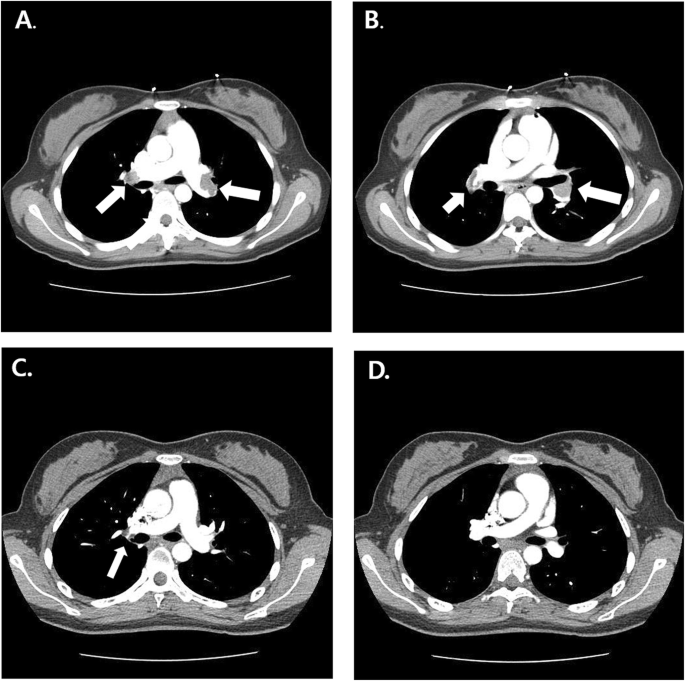

An 18-year-old girl presented to the emergency department in our hospital with syncopal attack for 30 s. The patient had experienced palpitation, external dyspnea and chest discomfort for a week before admission. She did not have recent history of trauma, immobilization and infectious disease. She did not have any known underlying disease and was not pregnant. She has never smoked, drunken alcohol, or taken oral contraceptive. She was alert but complained mild dizziness. Her neurologic examination showed normal findings. Her vital signs were as follows: blood pressure, 70/50 mmHg; pulse rate, 110 beats/minute; temperature, 36.5oC; respiratory rate, 34/min; and oxygen saturation, 94.3% in ambient conditions. Blood studies revealed the following: white blood cell count, 11,440/μL; hemoglobin, 14.4 g/dL; non-fasting glucose, 104 mg/dL; blood urea nitrogen, 13.1 mg/dL; creatinine, 0.7 mg/dL; aspartate transaminase, 118 IU/L; and alanine transaminase, 88 IU/L. A thyroid function test indicated a state of thyrotoxicosis [T3 236.5 ng/dL (normal range, 80–200), free T4 28 pg/mL (8.9–17.9), thyroid-stimulating hormone, 0.08 mIU/L (0.17–4.05), thyrotropin binding inhibiting immunoglobulins (TBII), less than 0.3 (0 – 1 IU/L)]. Several coagulation factors were abnormal [D-dimer, 6.77 mg/L (0–0.55); protein S activity, 18% (55–123); protein S antigen, 19.2% (50–150); protein C Ag, 76% (72–160); and protein C activity, 81% (70–130)]. Other immunological workup did not reveal any evidence of connective tissue disease or antiphospholipid syndrome. An electrocardiogram showed T wave inversions in the inferior and precordial leads (Fig. 1). Chest computed tomography (CT) showed massive PTE in both central pulmonary arteries and diffuse goiter (Fig. 2a, b). However, there were no DVT in lower extremities, upper extremities and jugular veins. An echocardiogram showed severe pulmonary hypertension (right ventricular systolic pressure (RVSP) = 64 mmHg), and a dilated RV, right atrium and main pulmonary artery (Fig. 3a-c). Therefore, the patient was diagnosed with massive PTE, thyrotoxicosis, and partial protein S deficiency. To manage the PTE, we administered low molecular weight heparin for 5 days and added warfarin while adjusting the prothrombin time such that the internal normalized ratio was between 2.0 and 3.0. On the 7th day after admission, she was discharged with oral warfarin and methimazole. A follow-up echocardiogram obtained 3 months after anticoagulation therapy demonstrated normal dimensions and systolic function of the RV and disappearance of the D-shaped left ventricle (LV) (Fig. 3d-f). After thyrotoxicosis was treated with methimazole for a month, a euthyroid state was achieved and the goiter decreased to a normal size (Fig. 4). The methimazole was gradually tapered off and stopped at 4 months. At a 6-month follow up visit, PTE and pulmonary hypertension had disappeared (Fig. 2c, d) but the patient still had a partial protein S deficiency. We decided to stop all medication with careful monitoring. During a 4-year follow-up period after the episode, she was asymptomatic without any evidence of recurrent systemic thromboembolism or hyperthyroidism and had still a partial protein S deficiency.

Chest computed tomography (CT) scan with contrast showing multifocal thromboemboli (White Arrow) in both pulmonary arteries (a and b). Repeated CT scan performed six months after anticoagulation therapy showing complete resolution of the thromboemboli of the main branches of both pulmonary arteries (c and d)